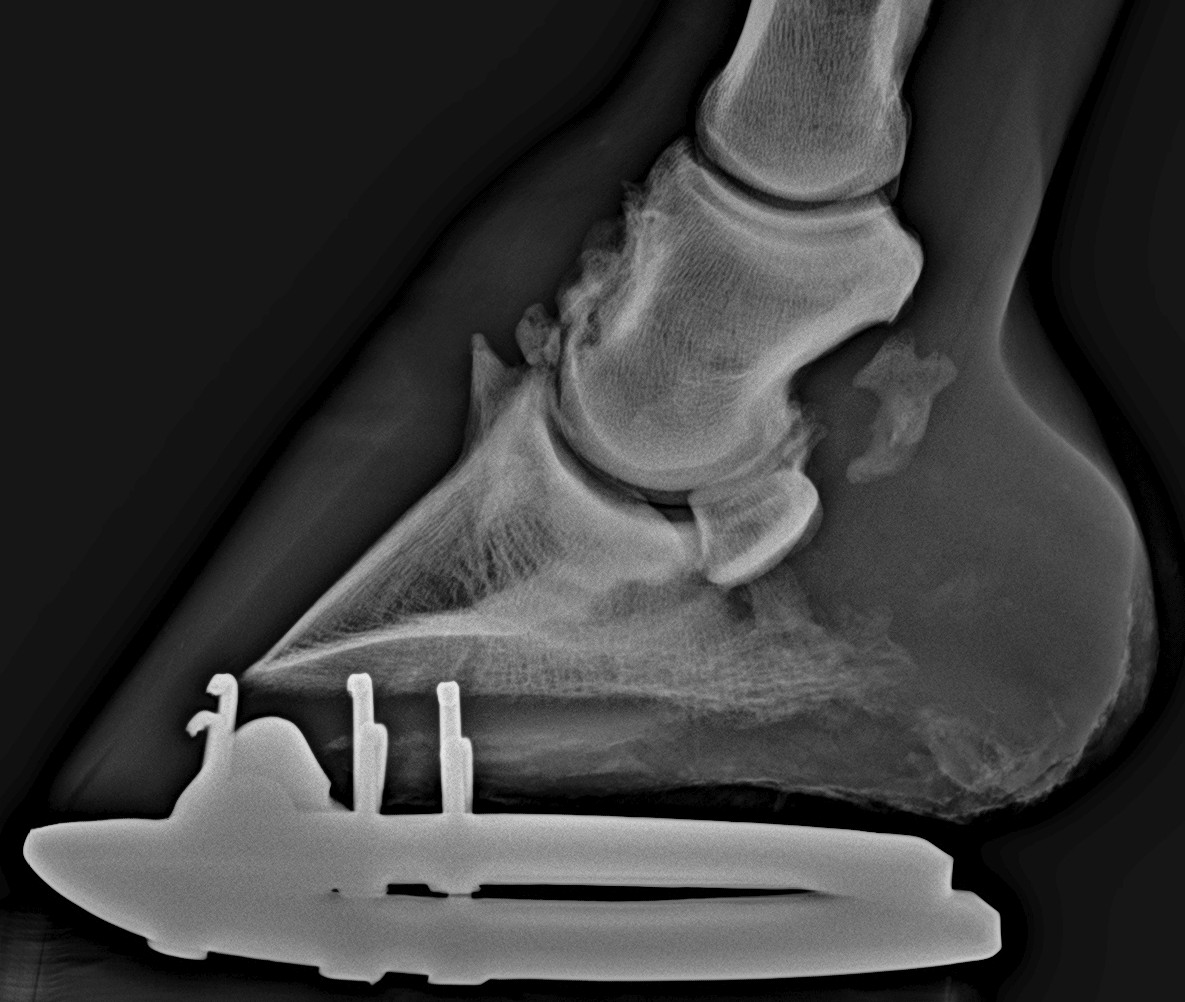

Súlyos ízületgyulladás. Rengeteg csontfelrakódás látható.